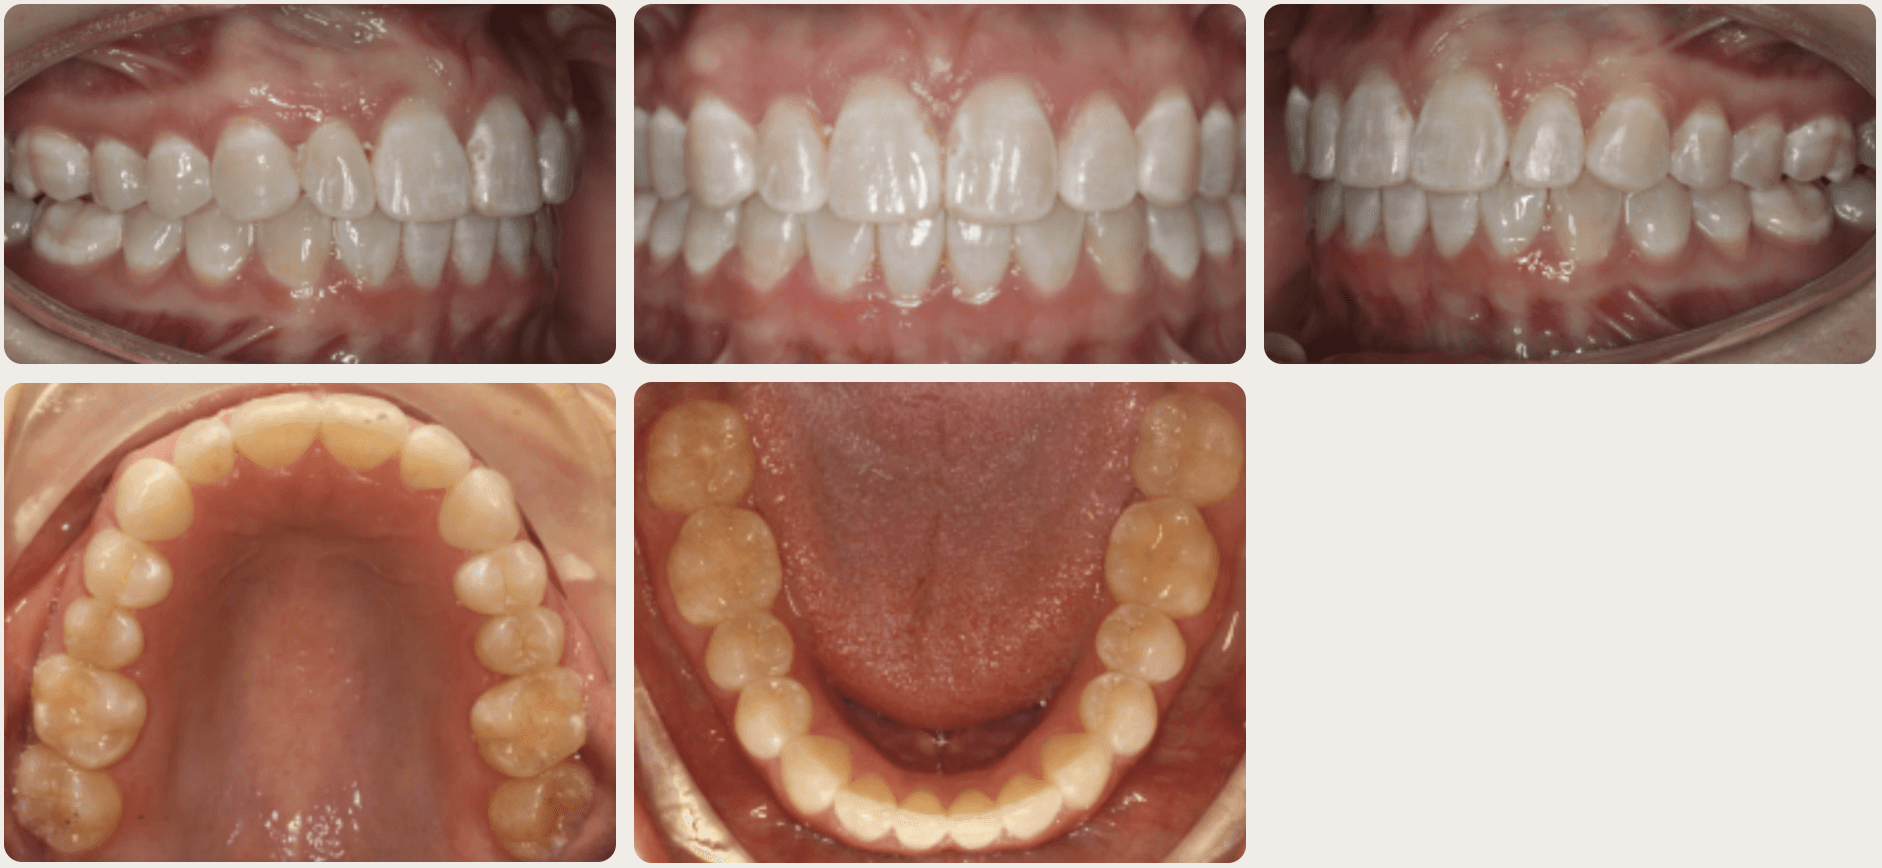

Final results

INTRAORAL